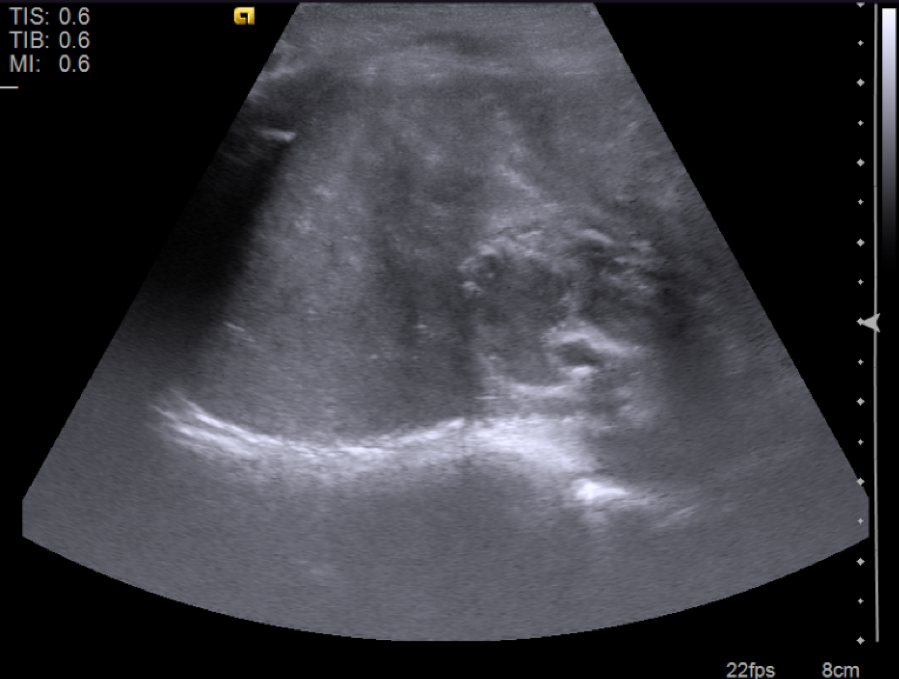

Radiology description

- Ultrasound

- Solid masses that are hyperechoic relative to the adjacent liver, although hypoechoic fibrotic septa can also be seen

- Epithelial hepatoblastomas may appear homogeneous

- Mixed epithelial / mesenchymal tumors exhibit heterogeneous imaging (due to osteoid, cartilaginous and fibrous tissue) and frequently have echogenic calcifications with acoustic shadowing and anechoic foci representing hemorrhage / necrosis (Radiol Bras 2017;50:68)

Radiology images